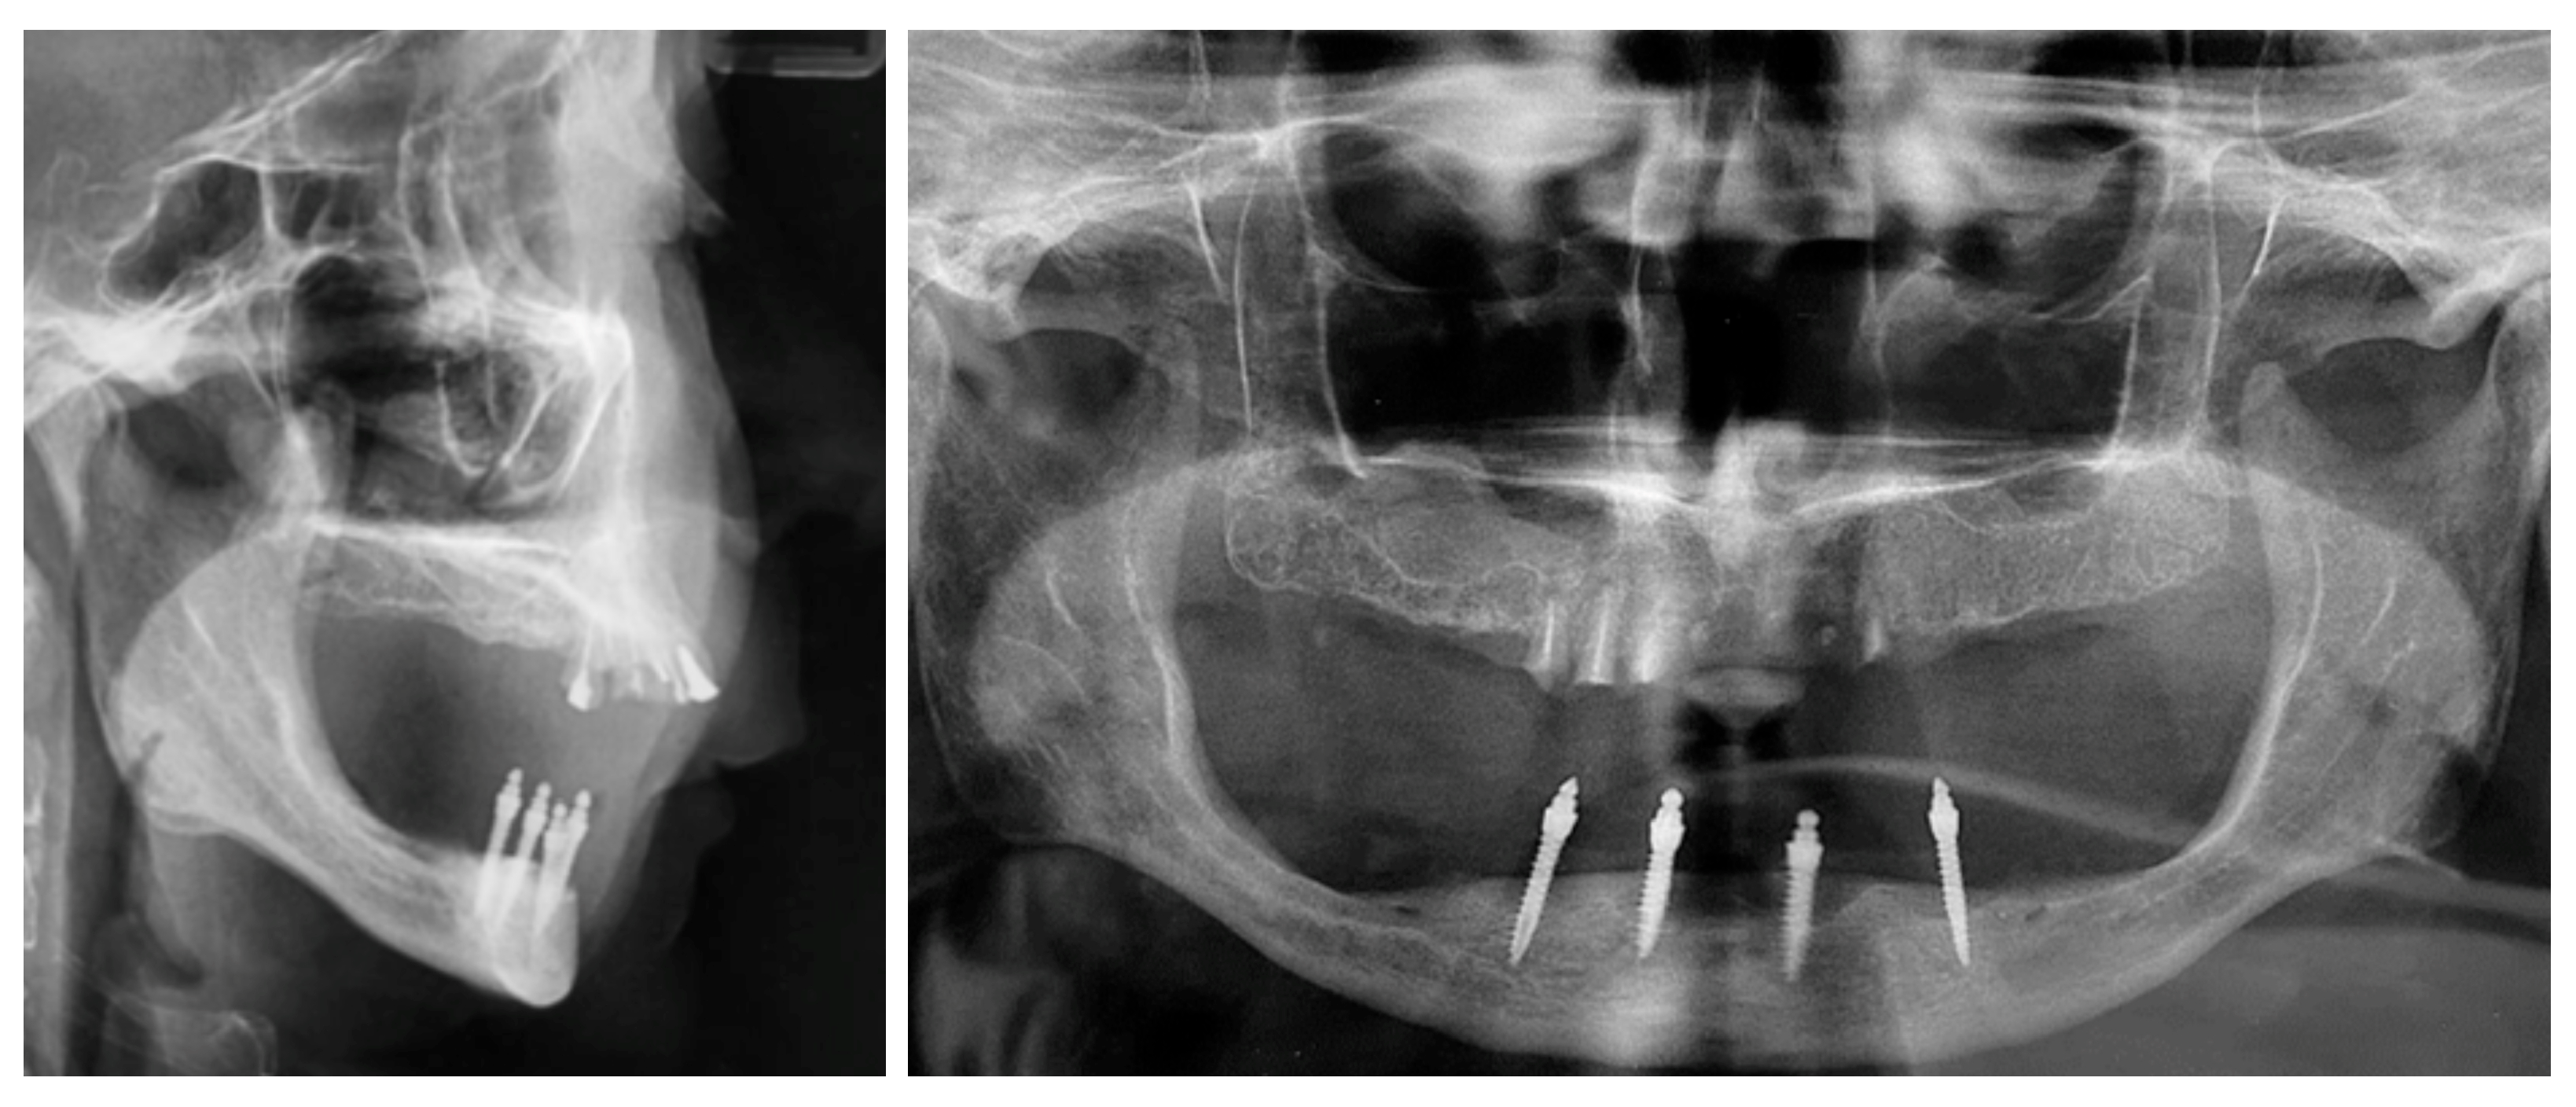

2.4. Prosthetic Alternatives for Managing Complications Associated with Ball Abutment Wear